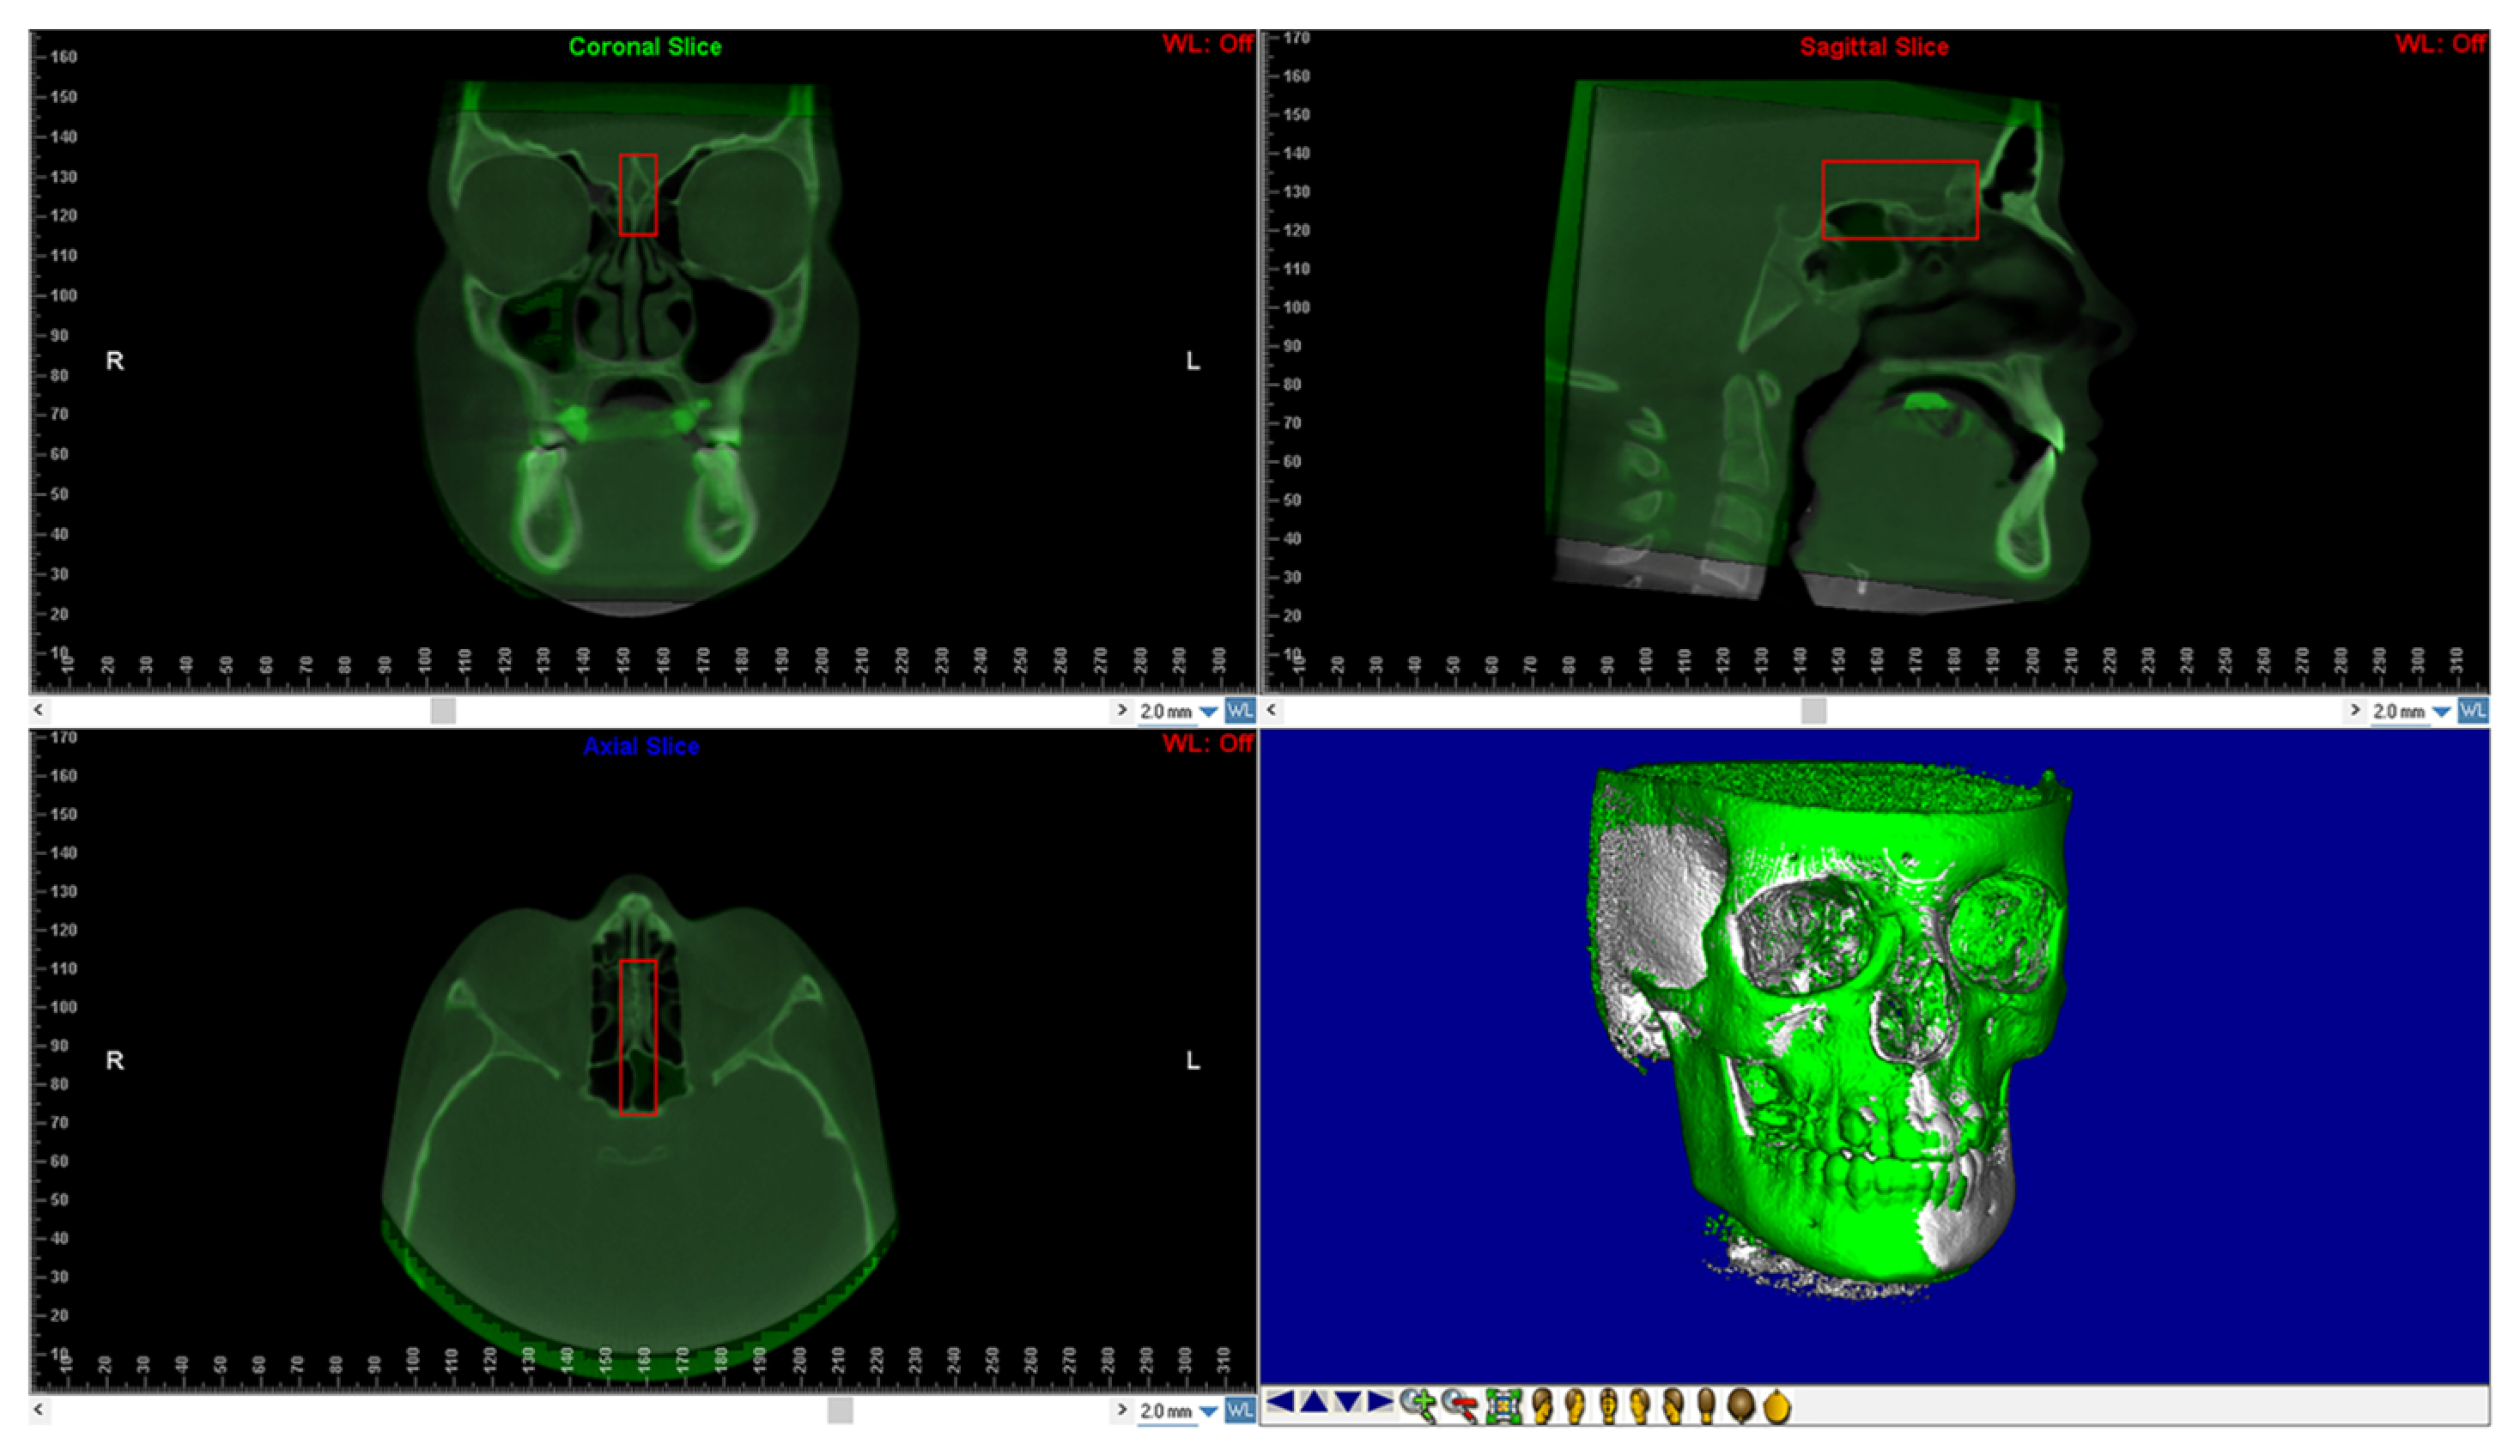

The reorientation of the CBCTs taken at T1 required the use of a voxel-based superimposition. The “sub-region box” in Dolphin program was used to pick the anterior cranial base region (Figure 2). The software matched the voxels of each CBCT in this region using thedefined edges and automatically superimposed them between T0 and T1. The CBCT obtained at T1 was then exported as a new DICOM file.

Figure 2.

Shows the anterior cranial base using voxel-based superimposition. The area of the cranial base to be used as a stable reference for the superimposition is defined in three dimensions using the red box.